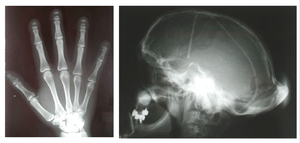

Hajdu–Cheney syndrome, also called acroosteolysis with osteoporosis and changes in skull and mandible, arthrodentoosteodysplasia, and Cheney syndrome,[1] is an extremely rare autosomal dominant congenital disorder[2][3] of the connective tissue characterized by severe and excessive bone resorption leading to osteoporosis and a wide range of other possible symptoms. Mutations in the NOTCH2 gene, identified in 2011, cause HCS. HCS is so rare that only about 70 cases have been reported worldwide, since the discovery of the syndrome in 1948.

Hajdu–Cheney syndrome causes many issues with an individual’s connective tissues. Some general characteristics of an individual with Hajdu–Cheney syndrome include bone flexibility and deformities, short stature, delayed acquisition of speech and motor skills, dolichocephalic skull, Wormian bone, small maxilla, hypoplastic frontal sinuses, basilar impression, joint laxity, bulbous finger tips, and severe osteoporosis. Wormian bone occurs when extra bones appear between cranial sutures. Fetuses with Hajdu–Cheney syndrome often will not be seen to unclench their hands on obstetrical ultrasound. They may also have low-set ears and their eyes may be farther apart than on a usual child, called hypertelorism. Children's heads can have some deformities in their shape and size (plagiocephaly). Early tooth loss and bone deformities, such as serpentine tibiae and fibulae, are also common in those affected.